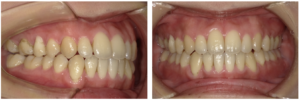

開咬の治療(インビザライン マウスピース矯正)

治療前

治療後

| 主訴 | 27歳女性 前歯で食べ物を噛みたい |

| 治療期間 | 2年6ヶ月 |

| 治療費 | 81万円+税(追加アライナー2回分を含む) |

| 治療内容 | インビザラインで矯正治療を行った。上下前歯の前方への傾斜、重度の叢生(凸凹)、舌癖(ぜつへき)による開咬を伴う症例であった。抜歯を望まれなかったので、隣接面削合(IPR)によりスペースを作り、叢生と開咬を解消した。 |

| 治療のリスク | マウスピースを規定の時間使用しないと、予定通りに治療を進めることが困難になり、治療期間が延長する。舌癖があるため、開咬が閉じない可能性がある。重度の叢生を非抜歯で治療することで、下顎前歯に歯肉退縮が生じる可能性がある。 |